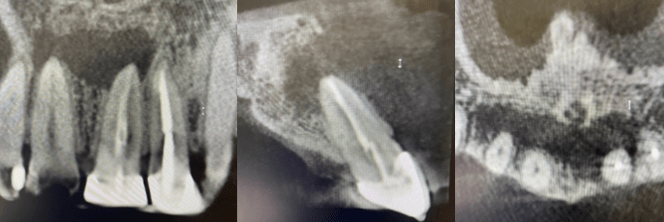

#18 NS-RCT

Dx: Asymptomatic Irreversible Pulpitis with NAT

#14 MB root amp with GTR

Dx: Previously Treated with CAA

#19 NS-RCT

Dx: Previously Initiated with SAP